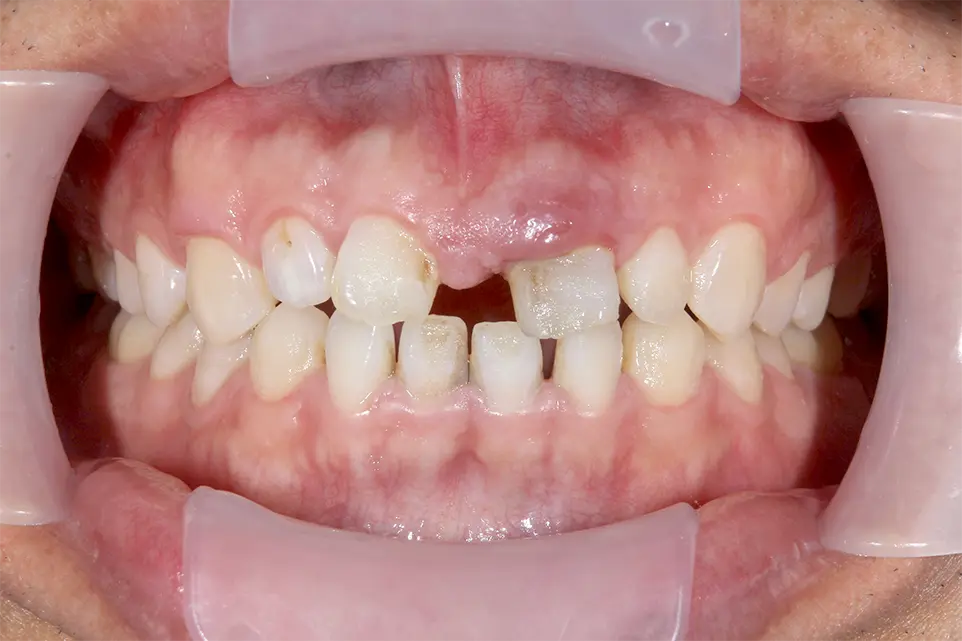

初診時

| 治療方法 | レントゲンで精査すると歯根が破折しており保存不可能なので抜歯。 もともと正中離開し審美的にも不良であった。正中離開した状態でそのまま治すのかこの際、審美的にも改善したいのか2つのオプションを提示すると矯正治療をした上で完璧に治したいとの要望があったので矯正治療を行いインプラント治療する計画を立てた。両隣在歯3本はジルコニアセラミック審美治療を行った。 |